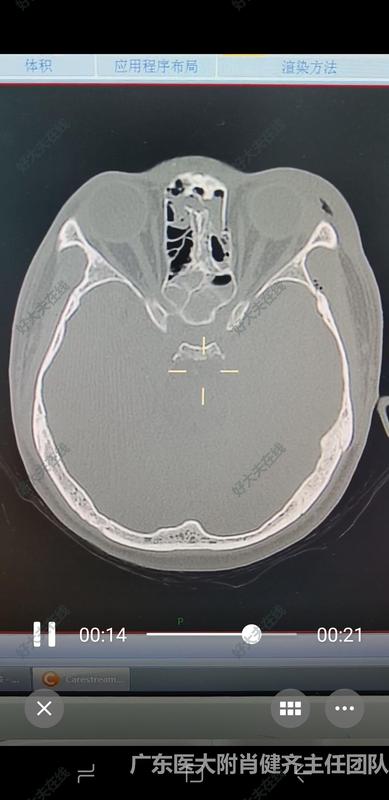

治療前 患者外傷以后,視神經(jīng)管骨折,蝶竇外側(cè)壁外側(cè)壁骨折,造成視神經(jīng)損傷,需要手術(shù)治療 治療后 治療后1月 視神經(jīng)管全程減壓?;颊邲](méi)有恢復(fù)光感,如果不做手術(shù),視力一定不會(huì)恢復(fù),現(xiàn)藥物治療,可能會(huì)有一定恢復(fù)性。